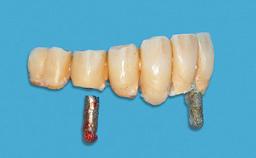

Prosthesis Type RDP

Defining Characteristics Fully edentulous lower jaw to be rehabilitated with an implant-borne removable overdenture

Loading Protocol Conventional/early